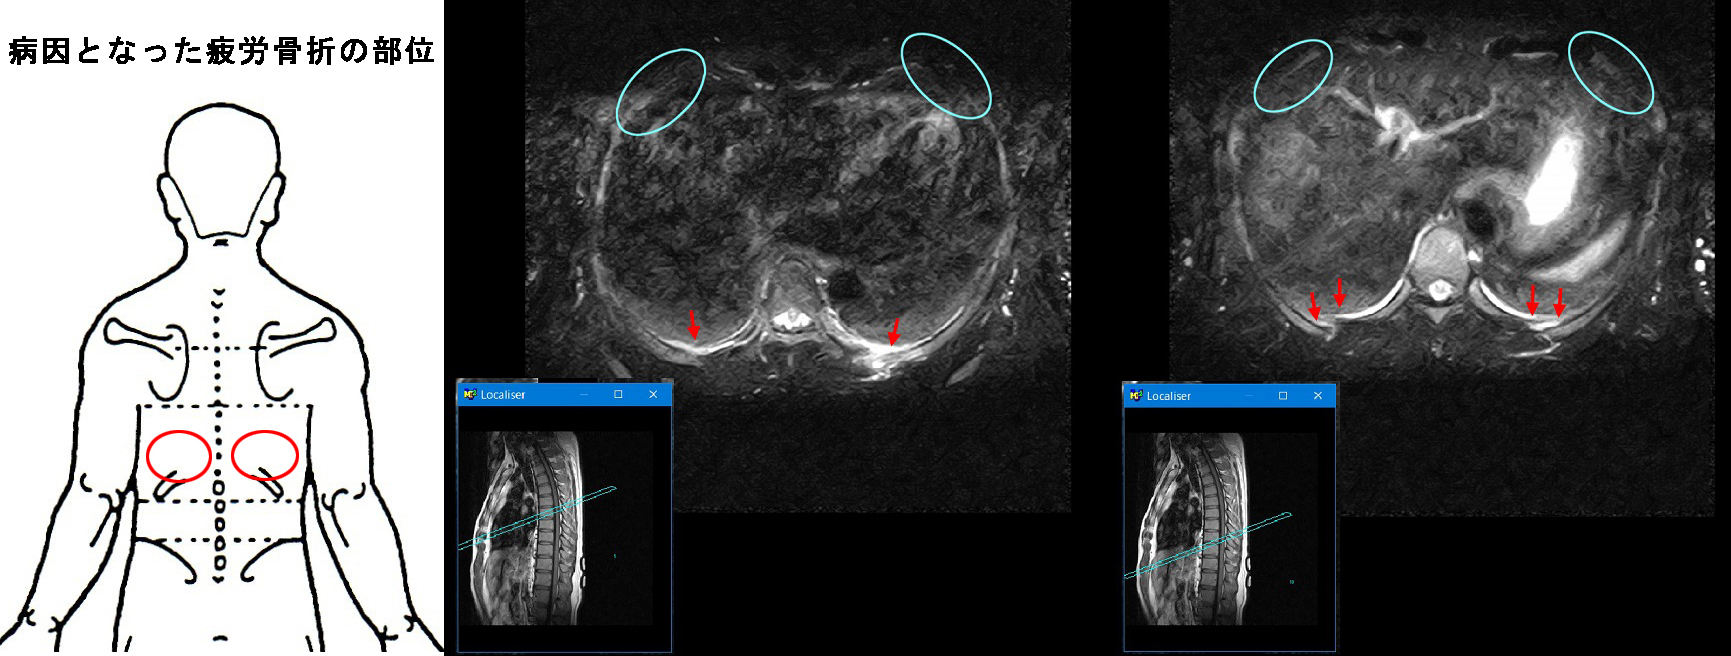

その病因は背側の両側肋骨の疲労骨折でした。疲労骨折は右下MRI画像の赤矢印部分です。

青丸が患者さんが痛みを訴えていた部位となります。

除染作業員・初診・疲労骨折部位2.jpg